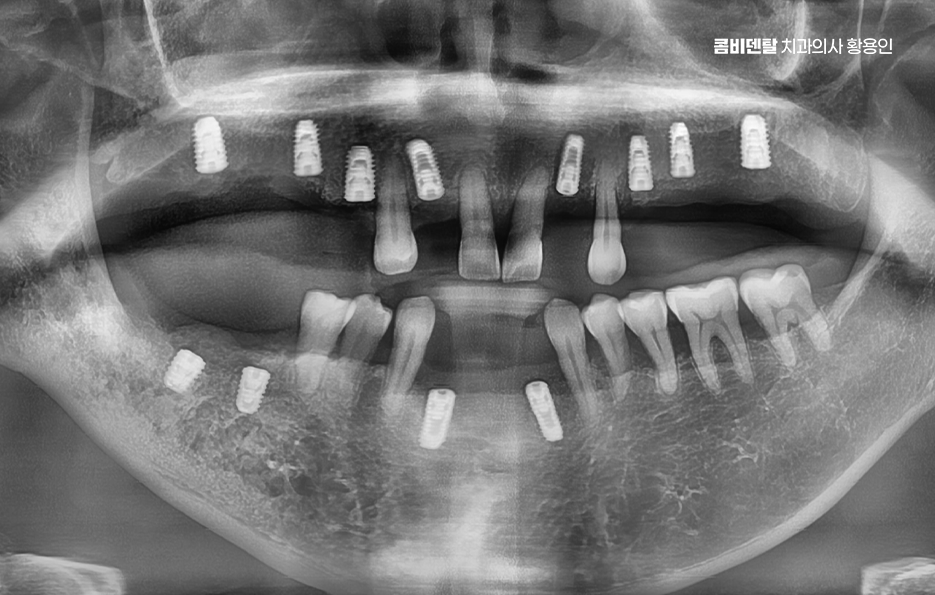

이런 상태를 “부분 무치악”이라고 부르는데 이러한 상태에서 50대임플란트 치료 계획을 세운다는 것은 전체 치열과 기능까지 다시 설계해야 하는 복잡한 치료가 될 수 있어서 50대에 여러 치아를 잃은 경우엔 임플란트 치료 계획이 단순한 ‘치아 대체’ 수준이 아니라, 전체적인 구강 재건이라는 개념으로 접근해야 할 수 있어요

50대임플란트 치료는 시작 전에 정밀한 진단이 선행되어야 하는데 단순히 빈자리만 보고 이 자리에 임플란트를 하나씩 심는 방식이 아니라 턱뼈 상태, 잇몸 높이, 씹는 힘의 분포, 전체 교합의 불균형까지 전부 고려해야 안정적이고 오래 가는 치료가 될 수 있어요

그래서 CT 촬영으로 턱뼈의 두께, 밀도, 신경 위치를 정밀하게 확인하고 각 임플란트의 위치와 각도를 계획해야 하며 50대는 전신 건강 상태도 함께 고려해야 하는데 당뇨, 고혈압, 골다공증 같은 만성 질환이 있는 경우에는 임플란트 치료 시 잇몸 치유 속도나 골융합 반응이 다를 수 있기 때문에, 반드시 의료진과의 충분한 상담이 필요하고 약물 복용 여부나 치유 능력 등을 고려해 치료 시기와 방식을 1:1 맞춤형으로 계획하실 필요가 있어요